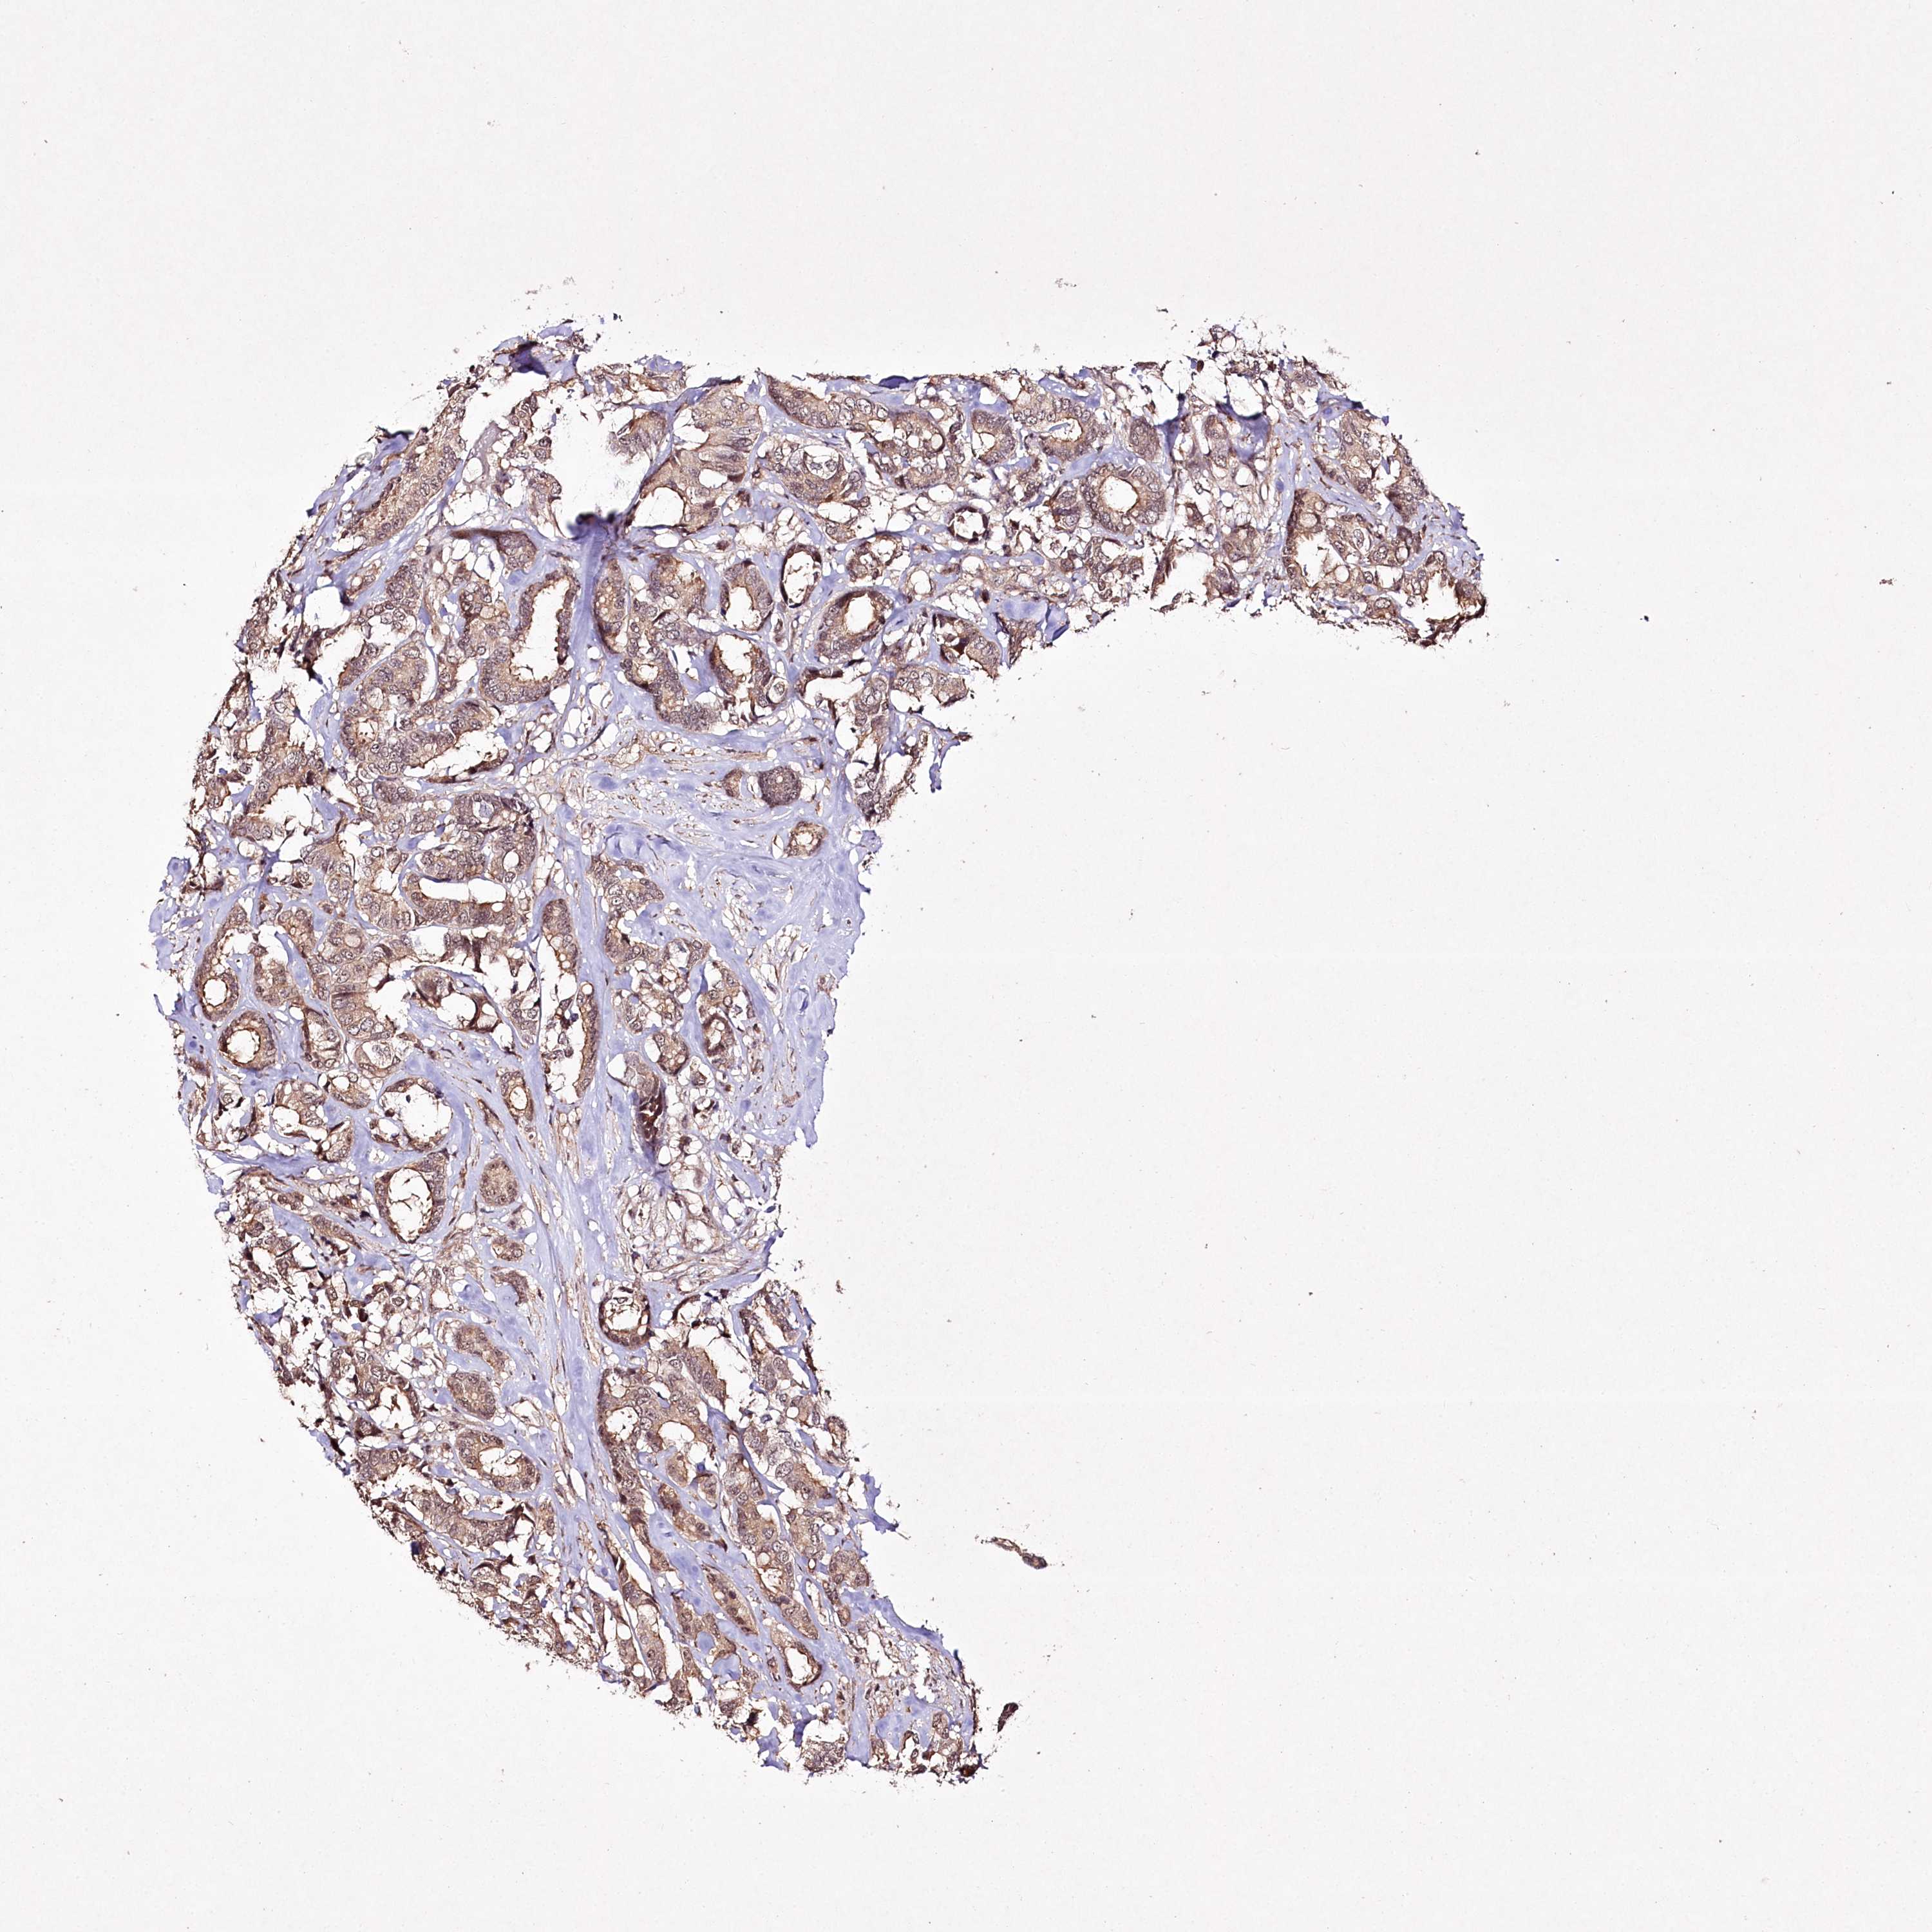

CANCER BREAST CANCER Show tissue menu

BRCA TCGA BRCA VALIDATION PROTEIN EXPRESSION

Breast cancer

Human cancer